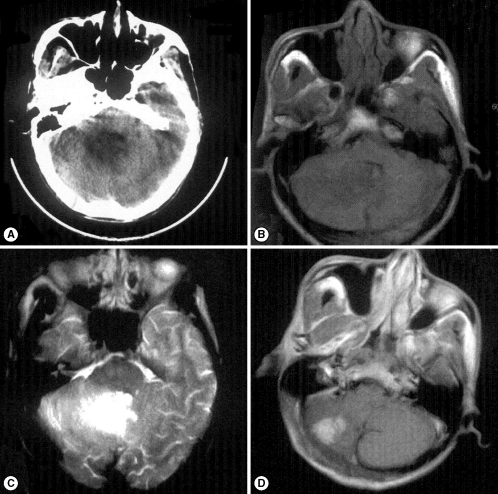

A 64-year-old, right-handed, herdsman was admitted to a hospital with mild headache, dizziness, and nausea for a few weeks. No fever, convulsion, or any other symptoms were accompanied. The herdsman came from Ganzi region in Sichuan province, an endemic area of S. japonicum in China. His medical history was unremarkable. During the previous few weeks he had experienced intermittent episodes of headache and nausea. On admission he was found to have slow mental functions, but no major neurologic dysfunction was detected. Laboratory findings revealed a leukocyte count of 13,000/ml, a normal RBC count, and no eosinophilia. The CSF revealed normal levels of protein, glucose, and chloride. Other studies in blood and CSF were normal. No parasite eggs were detected in stool. The results of chest radiography and abdominal ultrasonography were normal. Computed tomography (CT) of the brain showed edema areas in the right cerebellum (Fig. 1A). Brain magnetic resonance (MR) imaging was performed later and revealed isointense signals on T1-weighted images (Fig. 1B), hyperintense signals on T2-weighted images (Fig. 1C), and intensely enhancing nodules in the right cerebellum after intravenous administration of gadolinium (Fig. 1D).

The herdsman was treated with antibiotics for 14 days as the tendentious diagnosis of atypical brain abscess, but still complained of dizziness and aggravating headache. Then a high-grade glioma was suspected, and an operation of total resection was performed to solve the mass effect and intracranial hypertension. However, the examination of a frozen section of the biopsy tissue specimen suggested S. japonicum ova and granulomas (Fig. 2). Pathologic examination of the biopsy specimen revealed sclerosing schistosomal granulomas scattered within the parenchyma of the cerebellum. The diagnosis was confirmed, and the patient was treated with praziquantel at the dose of 20 mg/kg per day for 6 days, with concurrent administration of dexamethasone. The patient was discharged after 24 days and he was followed up 3 months later with complete resolution of the symptoms. However, the patient was lost to follow-up after a period of 6 months.

The diagnosis for brain schistosomiasis is difficult, as clinical findings are non-specific and laboratory changes such as eosinophilia and evidence of schistosome ova in stool or urine may or may not be present. Neuroimaging examinations can give significant help. The leptomeninges and cerebral cortex are the most common sites involved, whereas the cerebellum, thalamus, hippocampus, midbrain, basal ganglia, choroid plexus, and white matter are less frequently involved. In the mass form of brain schistosomiasis, CT typically reveals a nodular, enhancing, space-occupying lesion with surrounding edema, and contrast-enhanced T1-weighted MR images in many patients revealed a central linear enhancement surrounded by multiple enhancing punctate nodules, forming an "arborized" appearance. Pathologically, this enhancement pattern correlated with a host granulomatous response to schistosome eggs. Although the pattern is not present in all cases of brain schistosomiasis, when it is observed, a diagnosis of brain schistosomiasis should be considered [8].